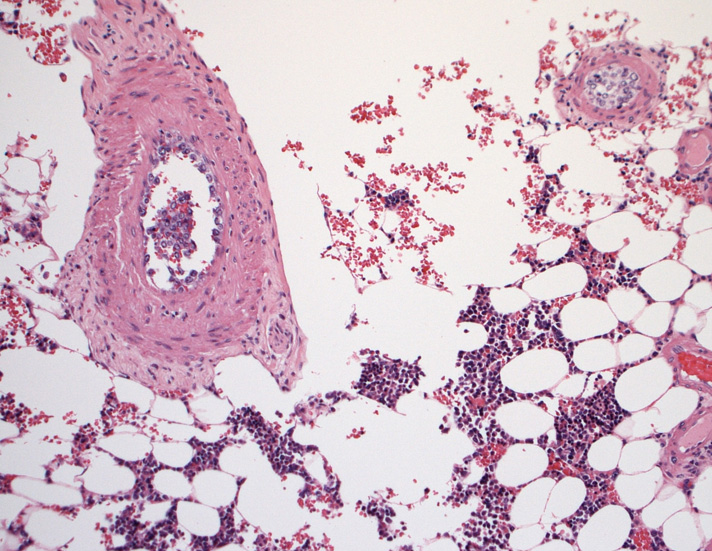

骨髄;細動脈内のみに腫瘍細胞が認められた。類洞や髄内での増殖は見られなかった。

骨髄穿刺吸引では発見できなかった原因のようです。骨髄生検で細動脈がとれないと診断に結びつかなかったでしょう。)